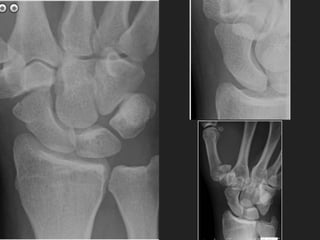

NAME THE #

WHICH WAY DOES THE

DISPLACEMENT GO?